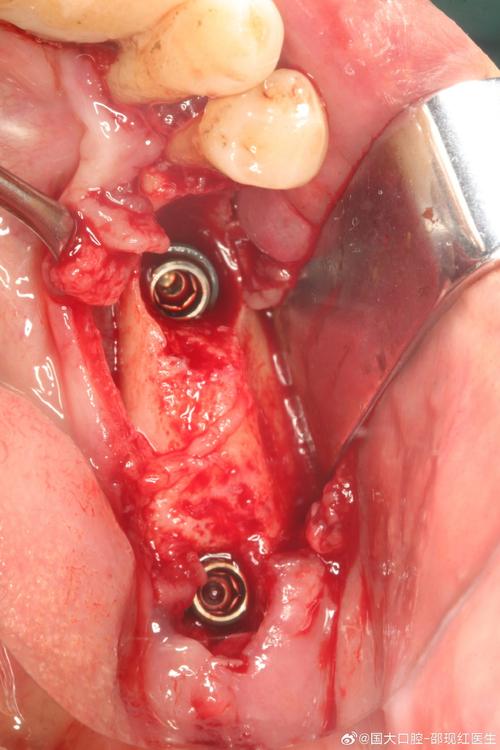

| 拔牙与窝洞预备 | 拔除患牙,彻底清创拔牙窝,去除炎症组织,修整骨壁 | 尽量保护牙槽骨壁完整性,避免过度搔刮,保留牙槽间隔,为种植体提供初期稳定性 |

| 种植体植入 | 选择合适直径、长度的种植体,植入拔牙窝,确保种植体尖端位于牙槽骨 cortical 下3-5mm | 种植体与骨壁紧密贴合,初期稳定性良好(扭矩≥35N·cm),避免邻牙损伤 |

| GBR(引导骨再生) | 若骨量轻微不足,可植入骨粉、骨膜,促进骨再生 | 严格隔湿,防止骨粉移位,确保生物膜覆盖骨缺损区 |